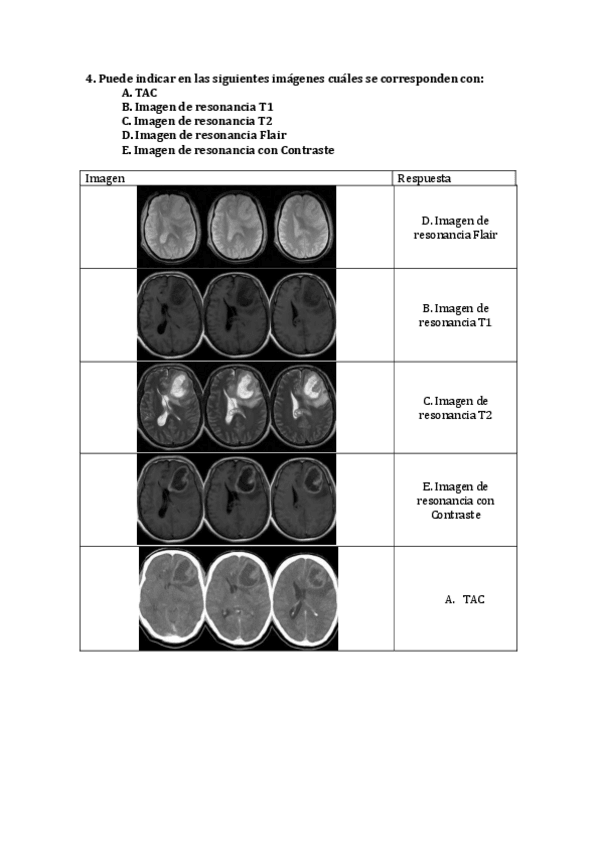

He publicado nuevos apuntes de 4º Neuropsicología Clínica: Tarea-Neuroimagen.pdf